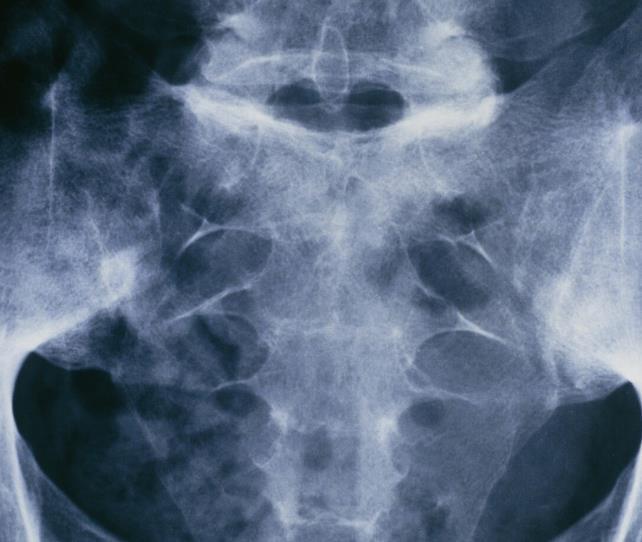

①?做骶髂关节片检查

一般骶髂关节会有问题.只要医生的徒手评估和检测,骶髂关节疼痛激发试验呈阳性,就非常有必要进行骶髂关节手术。关节的 X 射线或 CT 扫描。

骶髂关节放射学检查标准:Ⅰ级:骶髂关节正常; Ⅱ级:骶髂关节轻度异常,主要表现为骶髂关节有限的糜烂和硬化,但关节间隙正常; Ⅲ级:明显异常,骶髂关节糜烂、硬化,关节间隙增宽或变窄,部分强直; Ⅳ级:严重异常,表现为关节完全僵硬。

一旦骶髂关节单侧Ⅲ-Ⅳ级或双侧Ⅱ级以上,即可诊断骶髂关节炎,是关节内因素,不能干扰或改变状态.